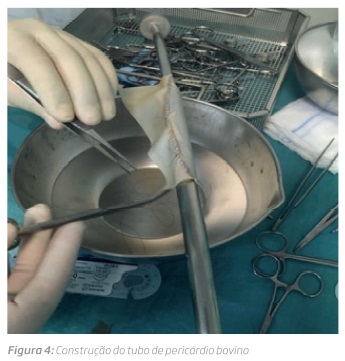

No dia 19/09 foi operado tendo sido realizado: excisão completa de prótese infetada, exclusão de fístula aorto-entérica duodenal (excisão de D2 e D3) seguido de duodeno-jejunostomia, construção de conduto biológico tubular com patch de pericárdio bovino (Patch biológico XenoSure, LeMaitre® 8x14cm). A sutura contínua foi realizada com prolene 4-0 (figura 4) e artérias femorais superficiais autólogas endarterectomizados ex-vivo obtendo um enxerto em Y (figura 5 e 6). A anastomose aórtica foi realizada em posição termino-terminal e as femorais em profundoplastia.

O pericárdio bovino é usado com frequência na cirurgia cardíaca e aórtica proximal e apresenta um bom comportamento no contexto de infeção com taxas de sobrevida livre de reinfeção de 80%(8). Também é usado no território carotídeo e femoral onde a literatura descreve muitos poucos casos de rotura ou formação de falsos aneurismas(9,10)

O recurso a xeno-enxertos tem a grande vantagem da sua disponibilidade imediata, ao contrário do homo-enxertos criopreservados. Além disso, usando como patch é possível a construção do tubo intra-operatoriamente sendo possível adaptar diferentes diâmetros de acordo com a anatomia do doente. A sua textura sólida, mas flexível confere-lhe ótima propriedade de manuseio tal como nos reporta Li et al.(11)